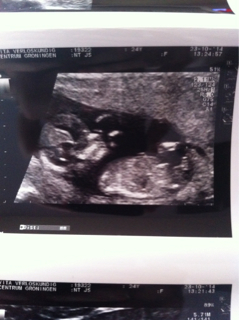

12 weeks 3 days.. Any one like to take a guess?? Nub

IF that is a nub I see, I'm going to lean girl (60/40) but really hard to tell. Congrats!

Girl lean here!:)

Leaning boy.

I think girl

girl

Girl lean but a bit ealryy

Leaning boy

Possible boy lean x

Opinion are divided I see haha. Have to wait till November 7th to find out! I'm so hoping for a boy :$ but ill be happy if it's a girl too..